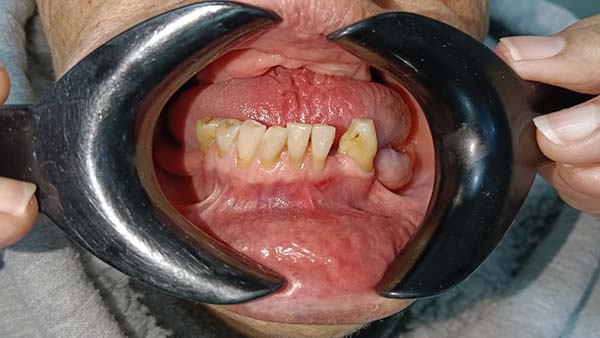

Comienza a cepillarte suavemente los otros dientes y usa hilo dental. No cepilles el área de la extracción durante los primeros días.

Puedes empezar a hacer enjuagues suaves con agua tibia y sal (1 cucharadita de sal en 1 litro de agua) o un enjuague bucal sin alcohol.

Evita el ejercicio físico intenso, ya que puede aumentar la presión arterial y causar sangrado.